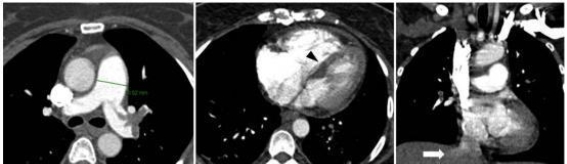

全麻下腹腔镜子宫切除术后急性肺栓塞的临床诊治

急性肺栓塞(PE)作为一种较为少见但极具致命性的围手术期并发症,给临床带来了巨大的挑战。尤其在全麻下进行腹腔镜手术时,由于症状隐匿且难以识别,PE的诊断往往受到...